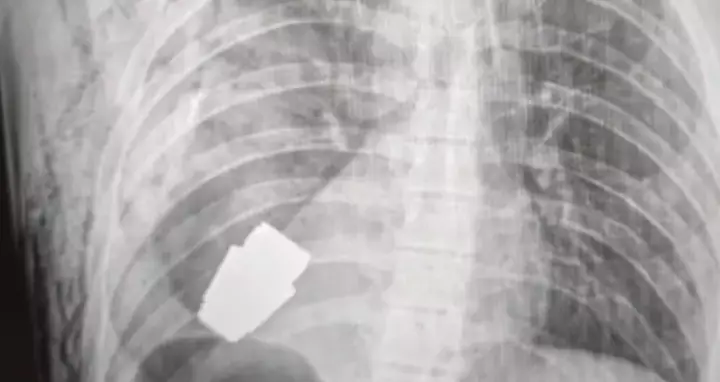

Images displaying an X-ray of the soldier’s chest were shared on the Facebook page of the Ukrainian armed forces medical service.

Another picture depicted a surgeon holding the device after successfully removing it from the soldier’s chest, where it had lodged near his heart.